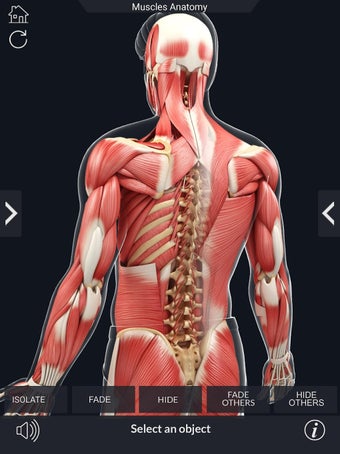

Den mest omfattande mobilappen som finns i världen för att studera muskelanatomi, som låter dig rotera 360°, zooma och flytta kameran runt en mycket realistisk 3D-modell.

Det finns mycket detaljer tillgängliga för varje muskel, vilket gör det till ett utmärkt verktyg för medicinstudenter.

Det finns många verktyg tillgängliga för varje muskel, inklusive:

- Göm och visa varje muskel separat.

- Rotera 360°.

- Zooma in och ut.

- Flytta kameran runt modellen.